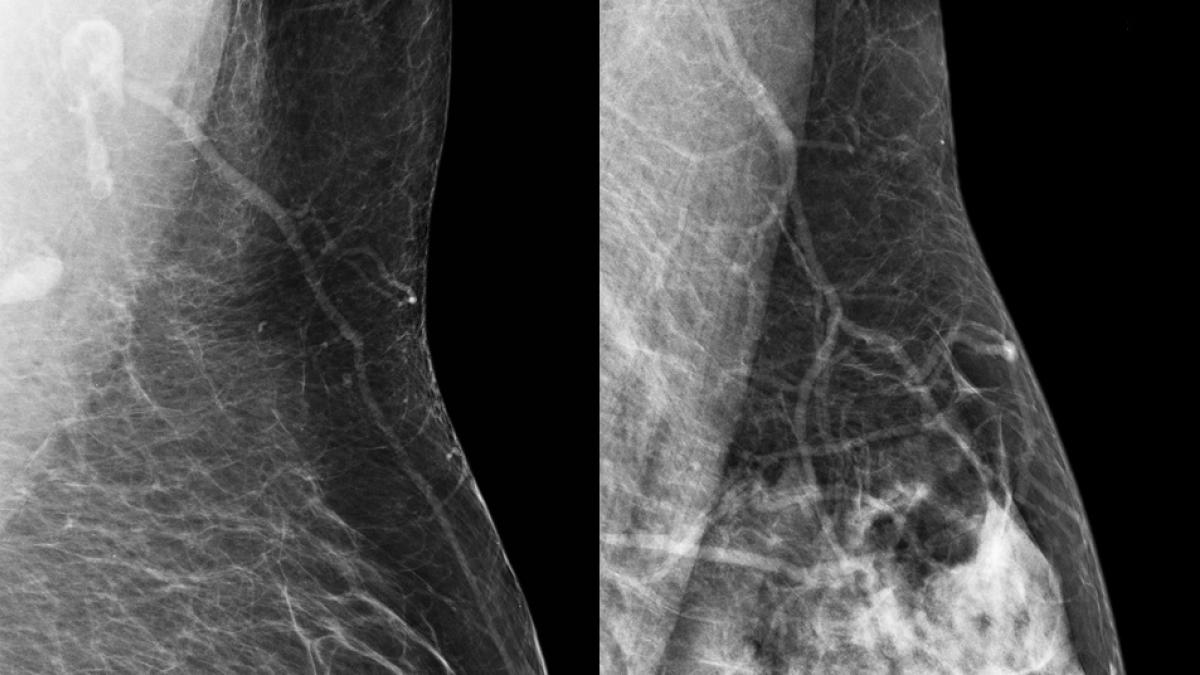

Al hacerse una mamografía, las imágenes desvelan cómo está compuesta la mama por dentro, y la proporción que existe entre los distintos tejidos que la forman, que son: glandular (las glándulas o lóbulos y los conductos que transportan la leche), fibroso (el que sostiene el tejido de las glándulas) y adiposo (la grasa que llena el espacio entre el tejido fibroso, los lóbulos y los conductos). Cuando la proporción de tejido fibroglandular (glandular y fibrosos) supera al graso, se dice que las mamas son densas.

En función de la densidad de las mamas, se clasifican en:

•Tipo A: Las mamas tienen casi en su totalidad tejido graso, algo que le ocurre al 10% de las mujeres.

•Tipo B: Unas pocas áreas de tejido denso están dispersas por todas las mamas. Alrededor de un 40% tienen este tipo de mama.

•Tipo C: Las mamas son uniformemente densas, algo que le pasa al 40 % de las mujeres.